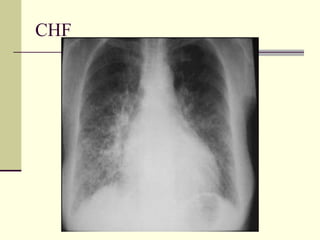

Pulmonary Interstitial Edema   1. CHF 2. Lymphangitic spread 3. Allergic reaction

CHF